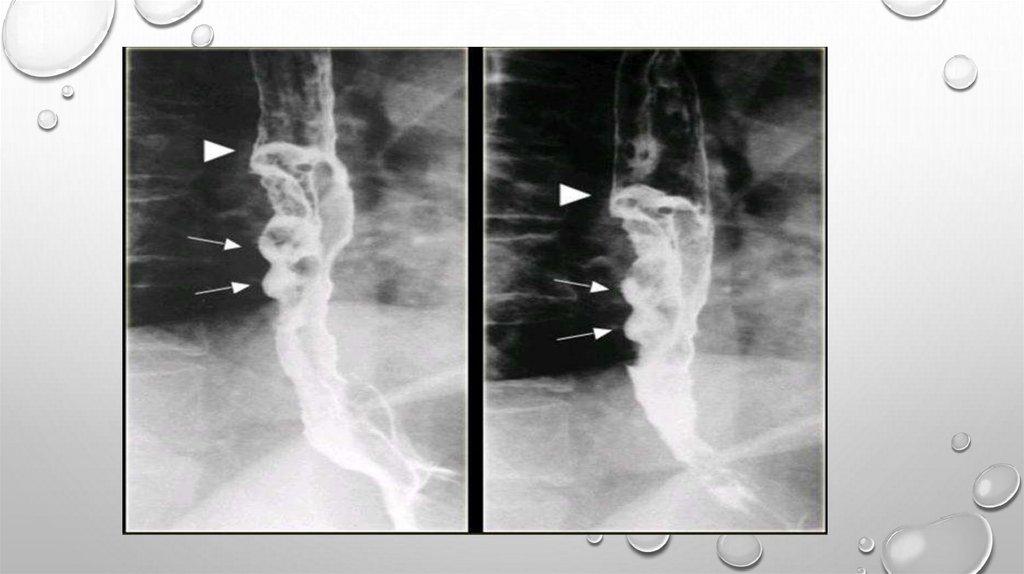

ДИАГНОСТИКА

РЕНТГЕНОЛОГИЧЕСКОЕ ИССЛЕДОВАНИЕ С

КОНТРАСТИРОВАНИЕМ ПИЩЕВОДА ВЗВЕСЬЮ БАРИЯ

ВЫЯВЛЯЕТ ОПУХОЛЬ, ЕЕ ЛОКАЛИЗАЦИЮ, ДЛИНУ

ПОРАЖЕНИЯ И СТЕПЕНЬ СУЖЕНИЯ ПИЩЕВОДА,

ИЗМЕНЕНИЯ В ЛЕГ КИХ И ПЛЕВРАЛЬНЫХ ПОЛОСТЯХ.

ХАРАКТЕРНЫЕ СИМПТОМЫ РАКА — ДЕФЕКТ

НАПОЛНЕНИЯ, "ИЗЪЕДЕННЫЕ" КОНТУРЫ ЕГО,

СУЖЕНИЕ ПРОСВЕТА, РИГИДНОСТЬ СТЕНОК

ПИЩЕВОДА, ОБРЫВ СКЛАДОК СЛИЗИСТОЙ ОБОЛОЧКИ

ВБЛИЗИ ОПУХОЛИ, ПРЕСТЕНОТИЧЕСКОЕ

РАСШИРЕНИЕ ПИЩЕВОДА.